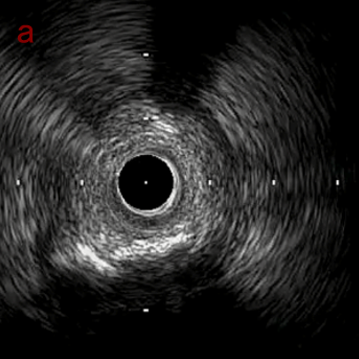

IVUS imaging

IVUSでは8時方向からPD枝がはいいてくる。

PreのIVUSではaの部位のみlipid plaqueを認め削ることでdistal embolismのリスクがあり、そのほかは270度の偏心性石灰化であるがwire biasは良好。